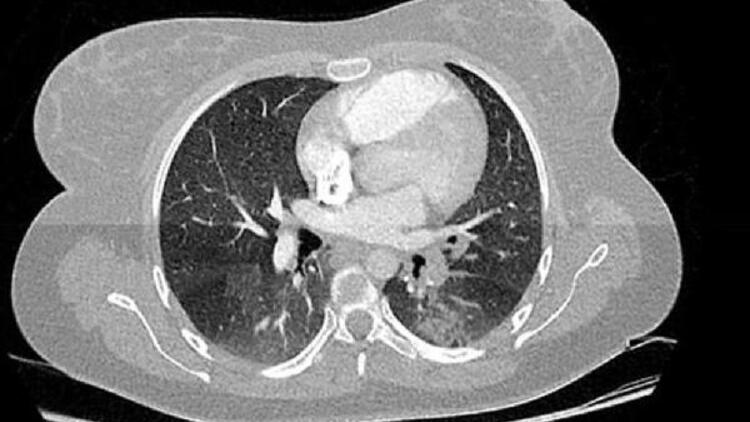

Fransa’nın Haut-Rhin bölgesindeki Colmar kentinde bulunan Albert Schweitzer Hastanesi'nden Dr.Michel Schmitt ve ekibi, 2019’un son aylarında çekilen binlerce göğüs filmini incelerken koronavirüs ile benzer iki bulgu belirledi.

Dr. Schmitt ve ekibinin 16 - 18 Kasım 2019 tarihleri arasında çekilen göğüs filmlerini analizi sırasında yaklaşık 2 bin 500 röntgende koronavirüs bulgularına benzer bulgular rastlandığı ifade edildi. Sonuçların henüz çıkarılamayacağını ve ekibinin virüsün yayılmasını haritalamak için Ekim'e kadar uzanan X-ışınlarına bakacağını söyleyen Dr. Schmitt , “Geleceği ancak geçmişi anlarsak yönetebiliriz. Bugün bu salgını açıkça anlamıyoruz. Bu hükümetin yönetim stratejisini tamamen değiştirebilir” dedi.